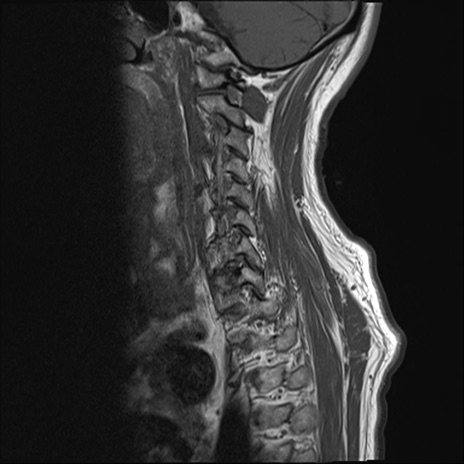

【整形】TIPS症例7 頚椎MRI T1WI(矢状断像)

頚椎MRI

T2WI(矢状断像)

矢状断像と横断像